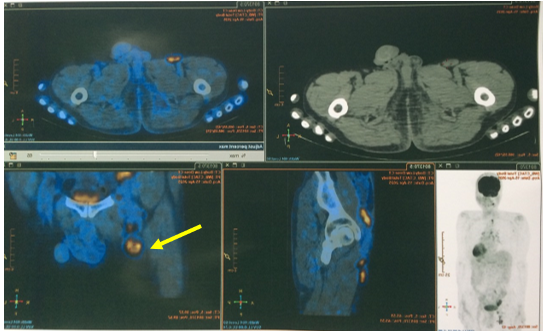

Hình 1: Nhu mô phân thùy VII có khối kích thước 37x35mm, ngấm thuốc thì động mạch, ngấm thêm vào trung tâm thì tĩnh mạch cửa,vùng trung tâm không thấy ngấm thuốc. (mũi tên vàng)

- PET/CT (Tháng 03/2025): Không thấy tổn thương tăng hấp thu FDG khu trú bất thường tại hạ họng. Hình ảnh hạch nhóm 1R, kích thước 12x15mm,tăng chuyển hóa glucose, khả năng do di căn. Đề nghị đối chiếu với mô bệnh học. Hình ảnh tổn thương giảm tỉ trọng kèm vôi hóa kích thước ~33x50x39mm, tăng chuyển hóa glucose ở hạ phân thuỳ VII gan, tương ứng với tổn thương gan đã nút mạch, theo dõi tiến triển. Hình ảnh nhiều hạch ở dọc theo động mạch chậu chung và chậu ngoài phải, bẹn phải, tăng chuyển hóa glucose. Đề nghị đối chiếu với mô bệnh học. Chưa phát hiện hình ảnh tăng hấp thu FDG bất thường, khu trú tại các vị trí khác trên xạ hình PET/CT toàn thân.

Hình 5: Hình ảnh hạch nhóm 1R, kích thước 12x15mm, tăng chuyển hóa glucose (SUV max 8,5), khả năng do di căn.(mũi tên vàng)